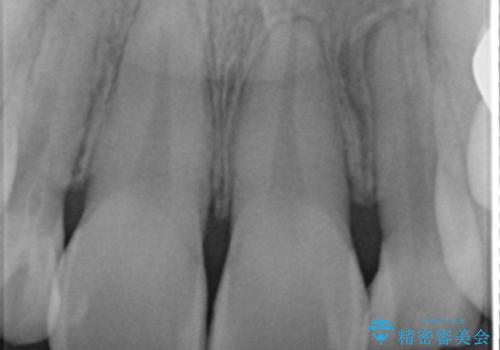

全顎的に歯並びにがたつきがあり、上の側切歯(上顎両側2)は生まれつき小さい歯(矮小歯)でした。

矯正治療後、矮小歯をセラミッククラウンにより理想的な歯の大きさに仕上げました。